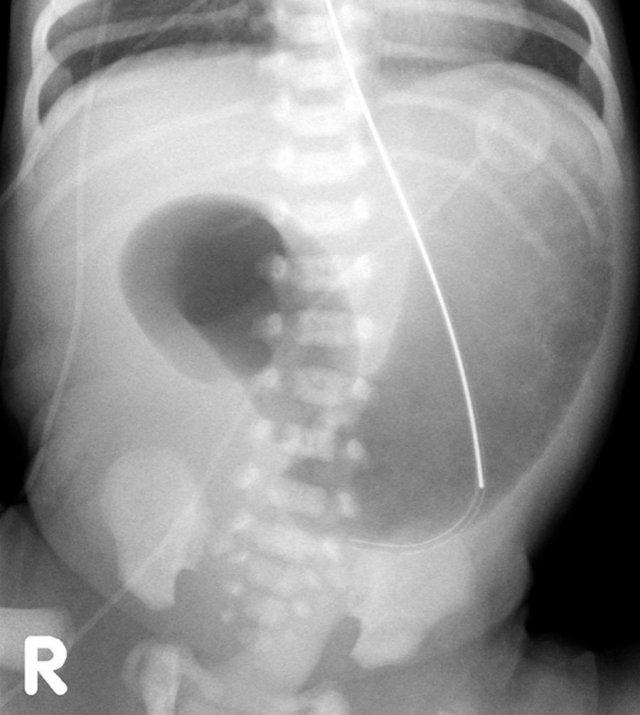

Đây là một trẻ sơ sinh bị xoay ruột bất thường.

Phim X-quang bụng không đặc hiệu (hình bên trái)

Chụp X-quang đường tiêu hóa trên cho thấy rõ ràng ruột non nằm bên phải cột sống.